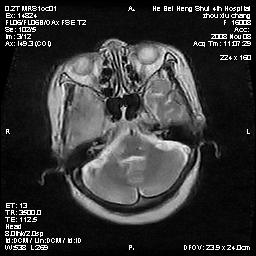

标题: MRI1883:女67岁,半年前曾患脑梗塞,治疗后好转,近3各月精

女67岁,半年前曾患脑梗塞,治疗后好转,近3各月精神恍惚。

形态及整体病灶看起来首先考虑转移瘤或淋巴瘤,但奇怪的是多个病灶周围均未见显著的水肿区,这不符合这两个肿瘤的特点,结合ct表现及患者病史有个人考虑是否有皮层下动脉硬化性脑病伴多发胶质增生可能.